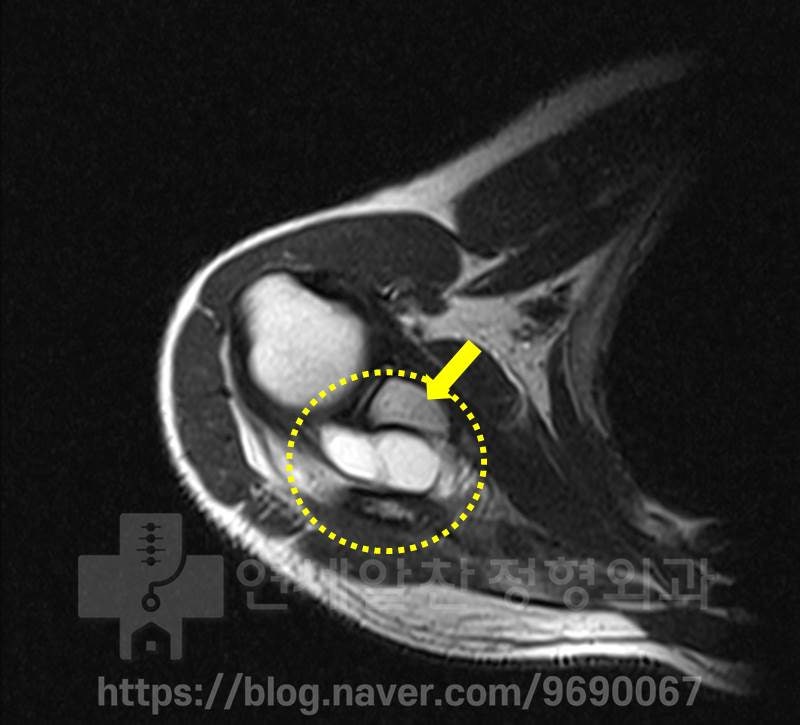

노란색 원형으로 표시된 부위의 하얀색 부위가 어깨 물혹입니다. 아주 커다란 어깨 물혹이 관찰됩니다. 하지만 관절와순의 손상은 관찰되지 않았습니다..